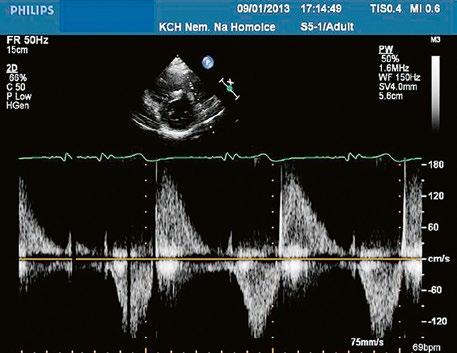

pravé komoře a sníženém tepovém objemu. Po provedené balonkové nebo chirurgické valvuloplastice v dětství bývá v dospělosti častá významná pulmonální regurgitace (Obr. 45.46, Obr. 45.47, Video 45.40).

Obr. 45.47 Stejný pacient jako na obrázku 45.46. PW dopplerovské vyšetření ukazuje v RVOT laminární nízkorychlostní zpětný tok při významné pulmonální regurgitaci po valvulotomii pulmonální stenózy v dětství.